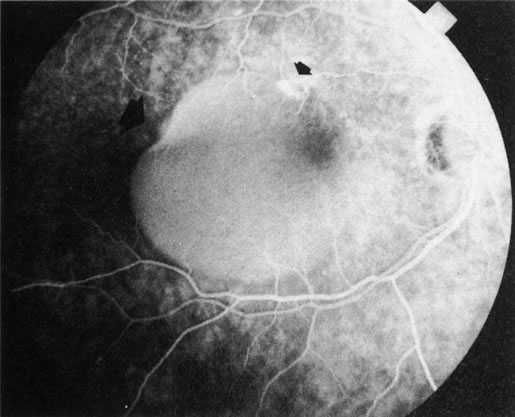

Age-related macular degeneration (AMD) may be divided into two types. Nonexudative (“dry”) AMD has several morphologic forms, including “hard” discrete drusen, shallow retinal pigment epithelial detachments associated with thickened Bruch's membrane (“soft” drusen), and geographic atrophy (GA) of the retinal pigment epithelium (RPE).3 On FA the area of GA appears hyperfluorescent for window defect from the early frames of the angiogram, with late staining of the underlying sclera (Fig. 1). However, these pathologic changes can usually be assessed by clinical examination, and FA is generally not necessary to diagnose nonexudative AMD. An exception is cuticular drusen, which may appear clinically as a subtle disturbance of the RPE; FA reveals multitudes of small, discrete drusen described as “stars in the sky” (Fig. 2). The second type of AMD, which is associated with soft drusen, is known as exudative (“wet”) AMD. It is due to a choroidal neovascular membrane that has incompetent vessels resulting in detachments of the RPE and the neurosensory retina. Consequently, in patients with a large RPE and/or serous neurosensory detachment, FA is often necessary to rule out a choroidal neovascularization (CNV). In general, a small pigment epithelium detachment (PED) and a larger neurosensory detachment overlie CNV, while the opposite is generally the case in a nonexudative PED. Additionally, CNV often presents as a “notched” PED (Fig. 3).4 The presence of subretinal blood or pigment at the border of a PED strongly indicates that the detachment is exudative in origin (Fig. 4). Similarly, a rip in the RPE generally reflects subretinal fibrosis from a CNV (Fig. 5 and 6). The diagnosis is more difficult in patients who have a chronic, organized PED. Such a lesion may be due to either nonexudative AMD or to an organized, fibrotic CNV. Clinically and angiographically, it may be impossible to distinguish between these two conditions. In most cases, however, FA does assist in making the diagnosis.

Fig. 3. Notched retinal pigment epithelium (RPE) detachment. There is a notch at the superotemporal border of a large RPE detachment that fills unevenly with fluorescein (large arrowhead). There is also a superior neovascular complex (small arrowhead) that hyperfluoresces. (Courtesy of Dr. Kenneth G. Noble.)